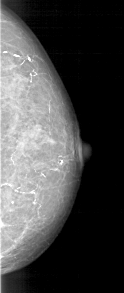

A_1191_1.RIGHT_MLO

RIGHT_MLO LINES 5491 PIXELS_PER_LINE 2116 BITS_PER_PIXEL 12 RESOLUTION 43.5 NON_OVERLAY